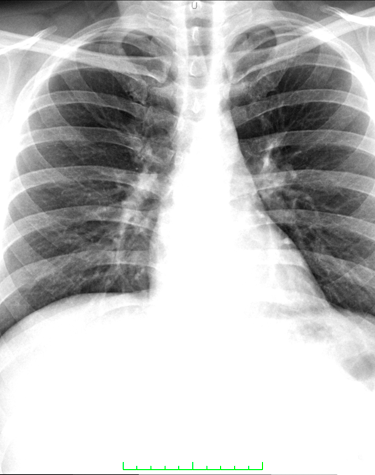

Radiología digital de alta calidad y precisión.

RADIOLOGIA GENERAL DIGITAL

Radiología Digital y Mamografia

Contamos con tecnología avanzada para diagnósticos precisos y confiables en radiología digital.

Galería Médica

Explora nuestros servicios de radiología y medicina regenerativa.